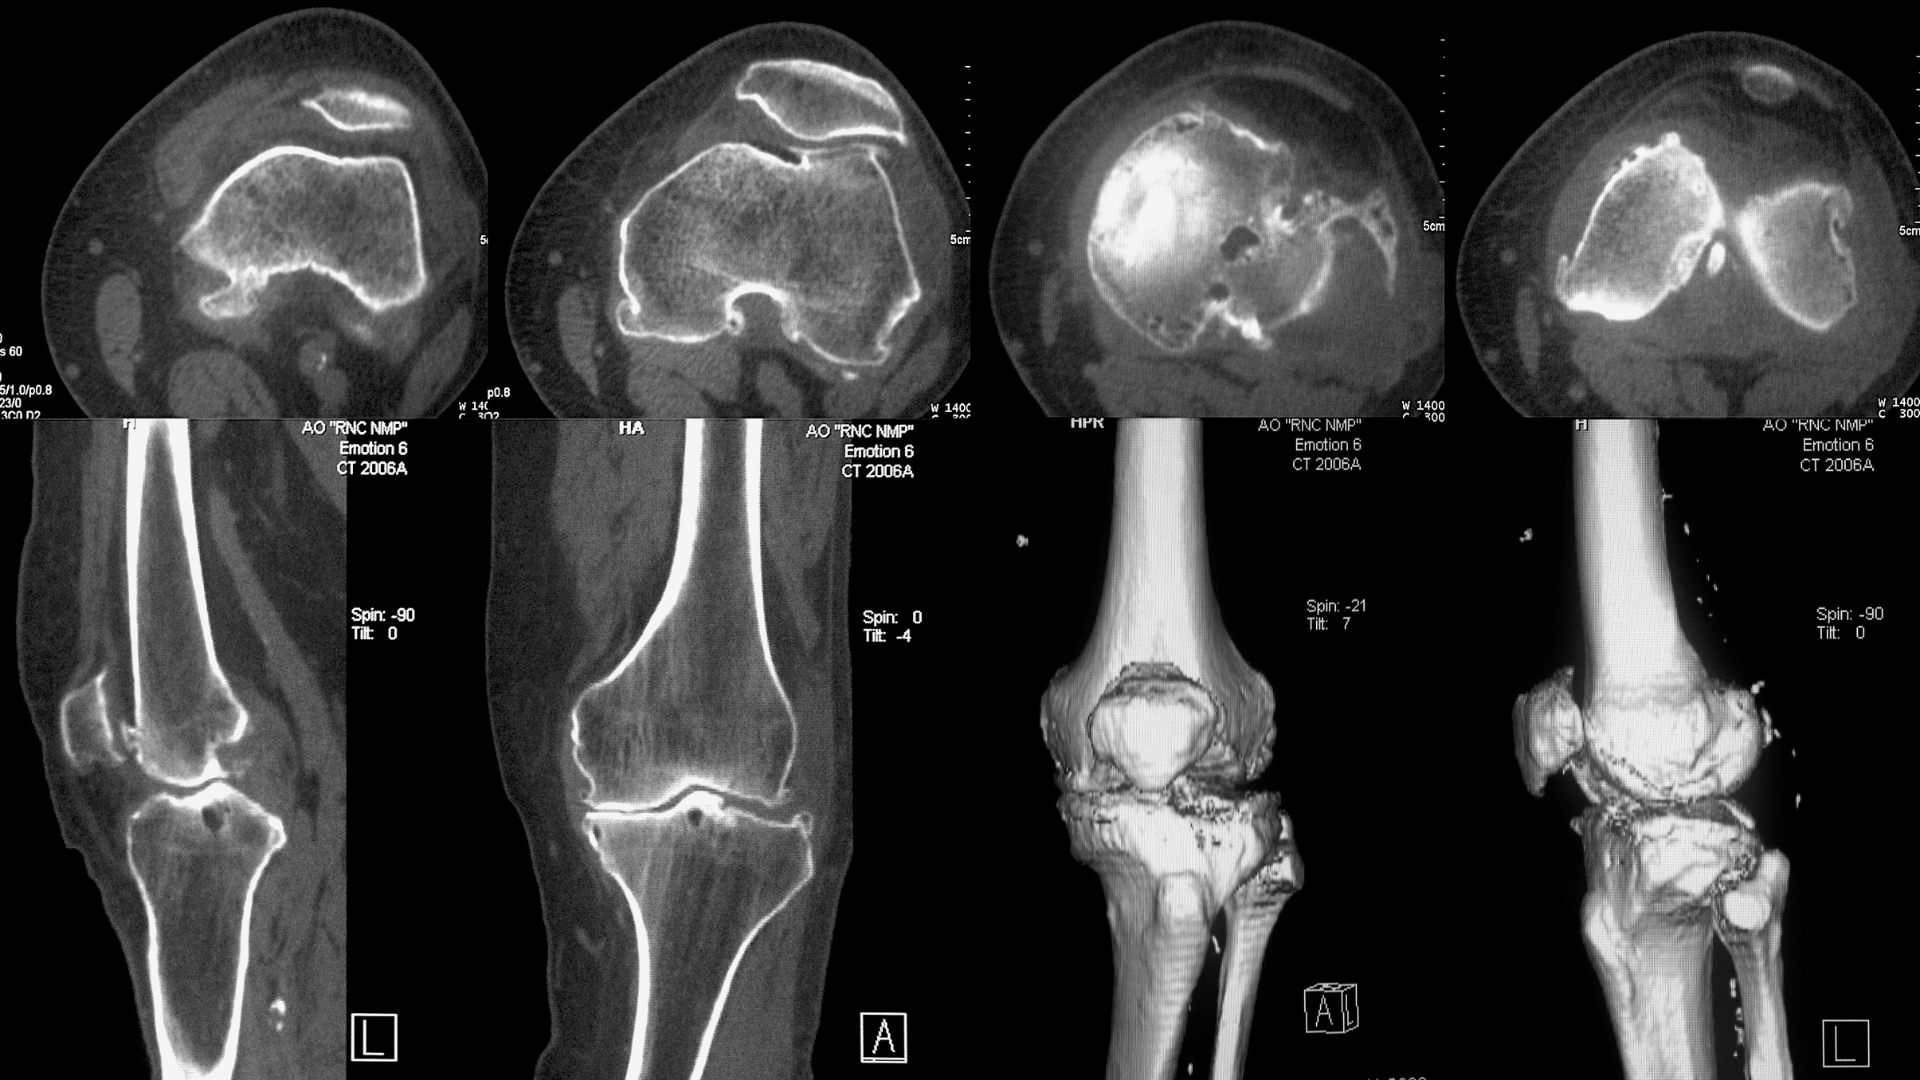

Chụp CT đầu gối là kỹ thuật chẩn đoán hình ảnh sử dụng tia X kết hợp với hệ thống xử lý máy tính để tạo ra các lát cắt chi tiết của khớp gối. Phương pháp này giúp quan sát rõ cấu trúc xương đùi, xương chày, xương bánh chè và các bề mặt khớp liên quan.

So với X-quang thông thường, CT đầu gối cung cấp hình ảnh chi tiết hơn, đặc biệt hiệu quả trong đánh giá các tổn thương xương phức tạp. Khi so sánh với MRI, CT có ưu thế trong khảo sát cấu trúc xương, phát hiện vôi hóa và các đường gãy nhỏ khó nhận biết.

CT đầu gối có giá trị cao trong chẩn đoán các loại gãy xương khớp gối, đặc biệt là:

- Gãy xương kín, gãy xương nhỏ khó thấy trên X-quang;

- Gãy lún mặt khớp;

- Gãy xương bánh chè;

- Tổn thương xương phức tạp sau tai nạn hoặc chấn thương thể thao.

Hình ảnh CT giúp bác sĩ đánh giá mức độ gãy, sự di lệch và ảnh hưởng đến bề mặt khớp, từ đó đưa ra hướng điều trị phù hợp.

Trong bệnh thoái hóa khớp gối, chụp CT đóng vai trò quan trọng trong việc đánh giá mức độ tổn thương cấu trúc xương. Phương pháp này giúp phát hiện rõ tình trạng hẹp khe khớp, hình thành gai xương, biến dạng bề mặt khớp cũng như tổn thương xương dưới sụn. Nhờ hình ảnh cắt lớp chi tiết, CT còn hỗ trợ nhận diện sớm các bất thường ở xương dưới sụn như hoại tử xương, lún xương hoặc những tổn thương vi thể khó quan sát bằng các phương pháp chẩn đoán hình ảnh thông thường, từ đó giúp bác sĩ đánh giá chính xác mức độ thoái hóa và lựa chọn hướng điều trị phù hợp.